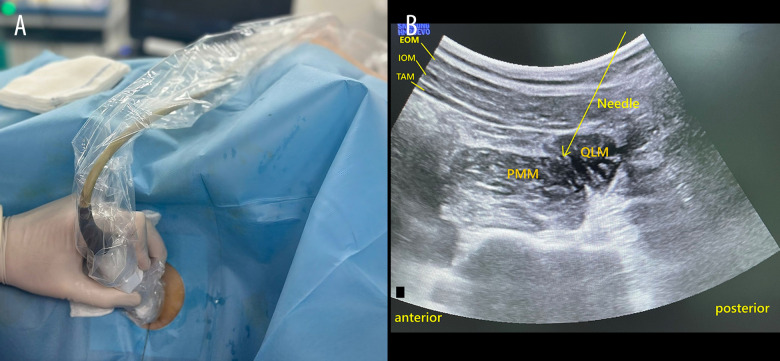

Abstract Image